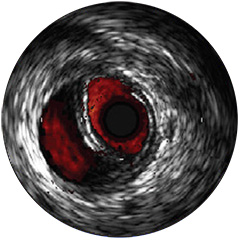

Figura 1